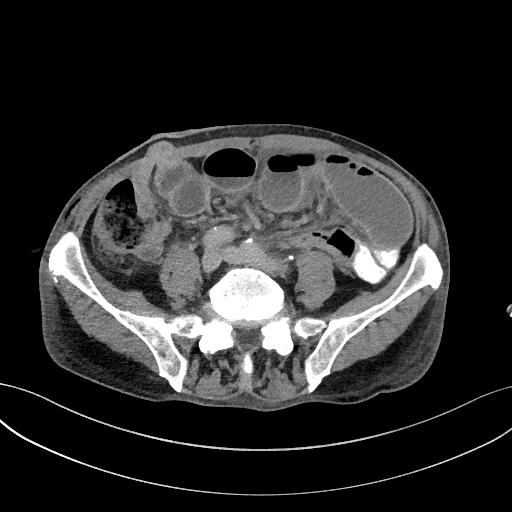

Figura 1: axial venos din achiziție CT torace, abdomen și pelvis

Discuţie caz nr 124: Pacient postoperator precoce pentru tumoră rectala prezintă simptome de ocluzie intestinală. Examinarea CT evidențiază creștere de calibru a anselor intestinale proximale ce conțin nivele hidro-aerice cu decalibrare la nivelul liniei antero-laterale de partea dreaptă unde evoluează o ansa de intestin subțire. Deasemenea, pacientul prezintă o hernie inghinală stânga fără ca aceasta sa fie cauză de ocluzie, precum și modificări postoperator precoce la nivelul peretelui anterior abdomino-pelvin.